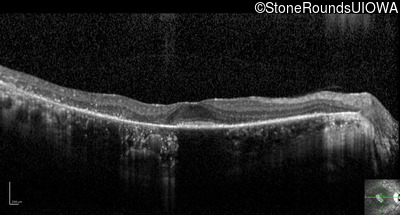

Optical Coherence Tomography - Right - 20/25

Exemplar / OCT Stack